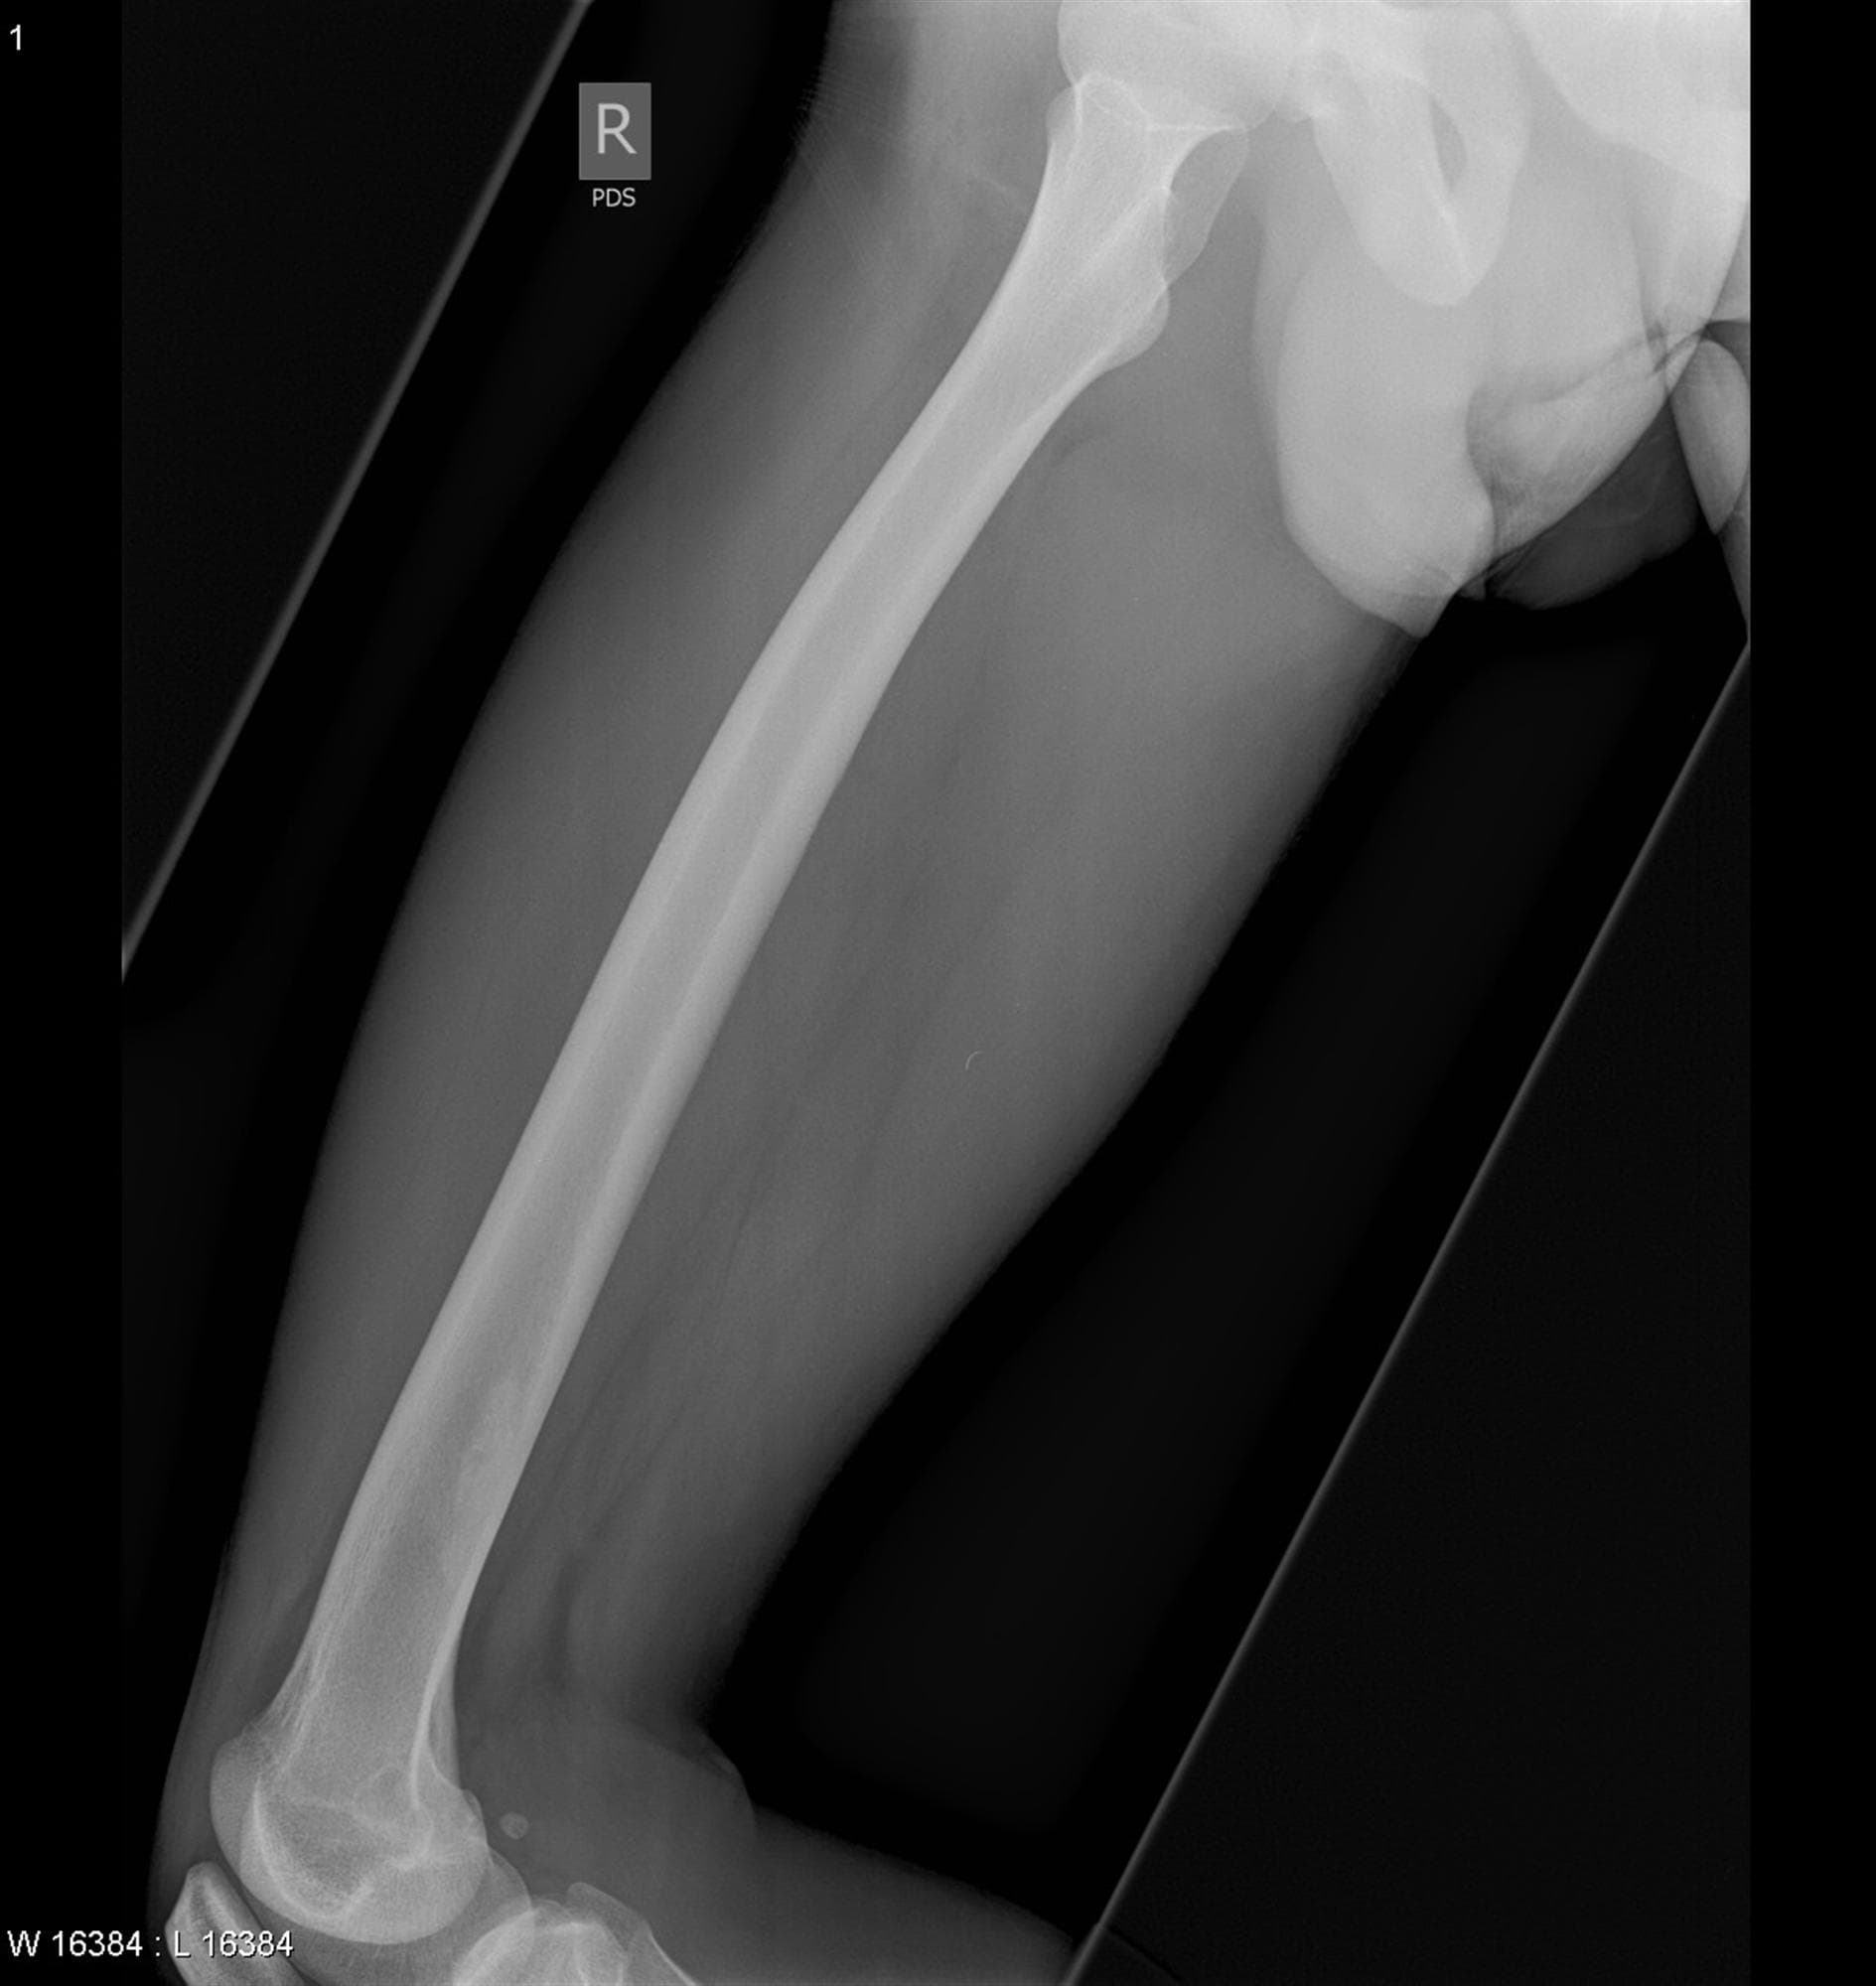

Femur Projections

Femur Projections Patient Preparation Explain the procedure to the patient.. Remove clothing and metallic objects from the area of interest.. Position the patient comfortably and immobilize the limb to prevent motion.. Use lead shielding as appropriate.. SID: Standard 100–120 cm (40–48 inches), ...

Read more →